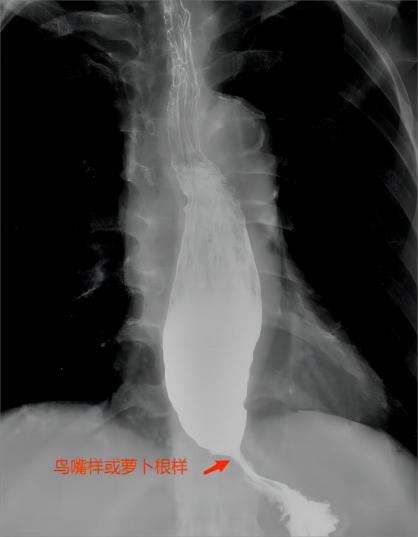

1.食管钡餐造影:是诊断贲门失弛缓常用的检查手段,方法简单,基层医院也能完成。患者喝下稀钡,通过和拍胸片类似的方式拍下一张黑白照片。它可以观察食管排空能力及胃食管交界部形态,但其诊断敏感度和准确度都只有80%左右,不如我们后面要介绍的检查高分辨食管测压高。它显示胃食管交界部狭窄呈“鸟嘴”样或“萝卜根样”(见图3),及钡剂排空不良,严重者食管可呈“S”型。

图3